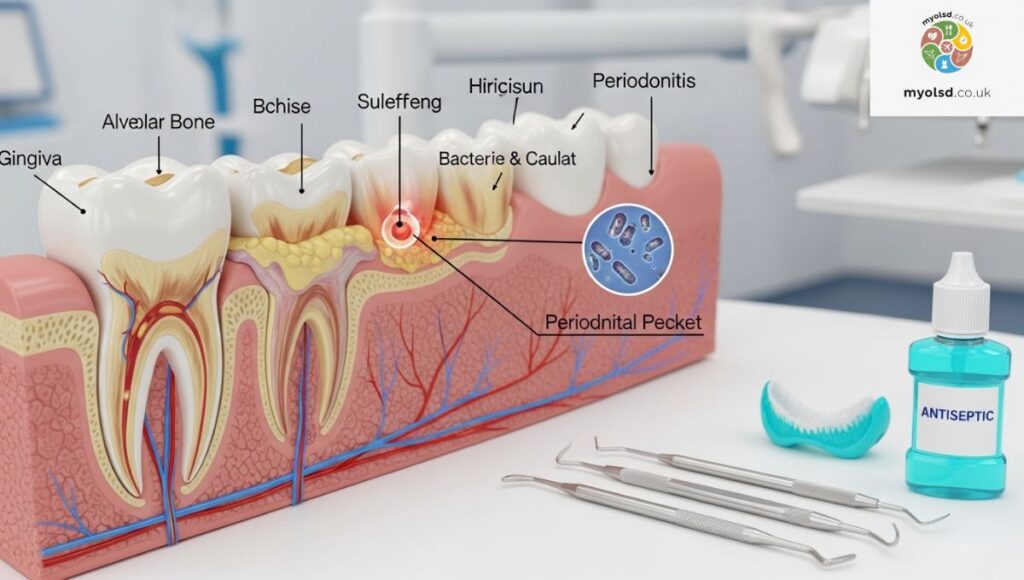

However, despite its importance, many people don’t floss as often as they should. This neglect allows plaque bacteria to build up, harden into tartar, and inflame your gum tissue, leading to gingivitis or even periodontitis in severe cases. Flossing helps keep your gum health in check and protects the foundation of your teeth.

4. Gum Disease and Tooth Decay

When gums are inflamed or infected, even gentle flossing can cause discomfort. Conditions like gingivitis or periodontitis make the tissue sensitive to pressure and touch. If your pain persists despite gentle technique, visit a dental professional for a full evaluation. You may have underlying tooth decay or infection that needs attention.

Gum Disease or Gum Recession

Early gum disease (gingivitis) can cause your gums to bleed and feel sore when touched. If untreated, it can lead to gum recession, where tissue pulls away from the tooth, exposing roots. This makes flossing painful and teeth more sensitive.

Underlying Dental Health Issues

Conditions like tooth infections, abscesses, or bone loss from periodontal disease can make flossing painful. If the pain is localized to one area or gets worse, see your dentist as soon as possible.

Even with a perfect home care routine, you can’t remove all tartar or bacteria at home. Regular professional cleanings remove buildup from under the gumline and prevent serious conditions like periodontitis. Aim for dental visits every 6 months or more often if your dentist recommends it.

How to Treat Gum Infections

If your pain worsens, you may have a gum infection or abscess. Seek prompt care from a periodontal specialist. They may prescribe antibiotics or perform a cleaning called scaling and root planing to remove bacteria beneath the surface.